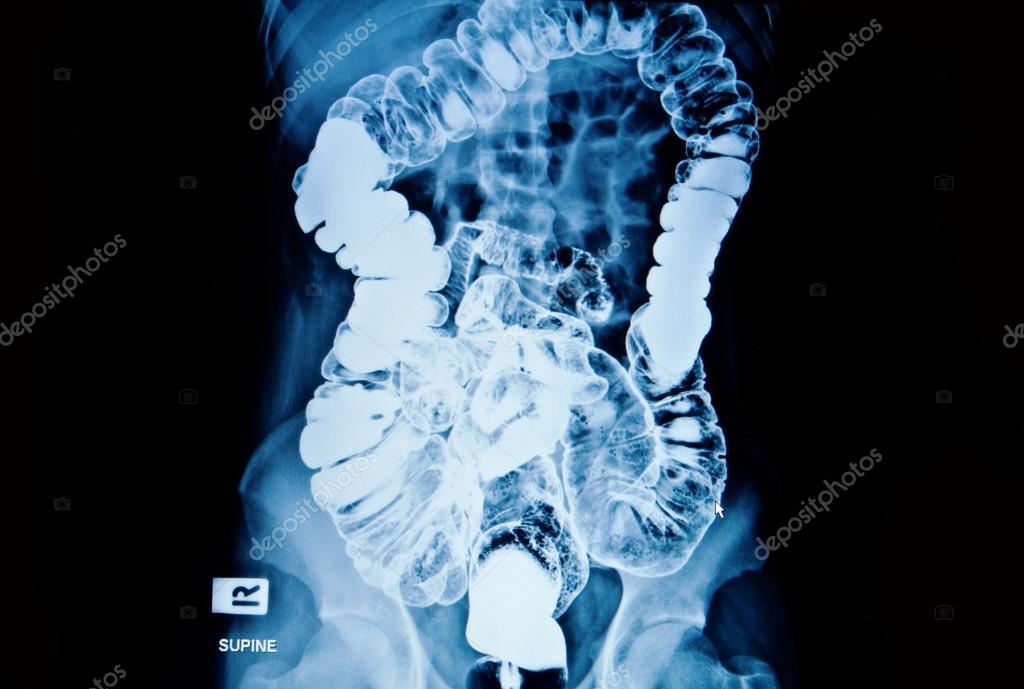

From depositphotos.com

Barium enema of a man demonstrated the normal rectum and cecum — Stock Is Barium X Ray Dangerous Modified barium swallow studies (mbsss) are a fluoroscopic exam that exposes patients to ionizing radiation. You may want to ask your healthcare provider about the amount of radiation used during the swallowing test. Why you might have it. You should ask your healthcare provider about the risks as they apply to you. Barium liquid does not do you any harm. Is Barium X Ray Dangerous.